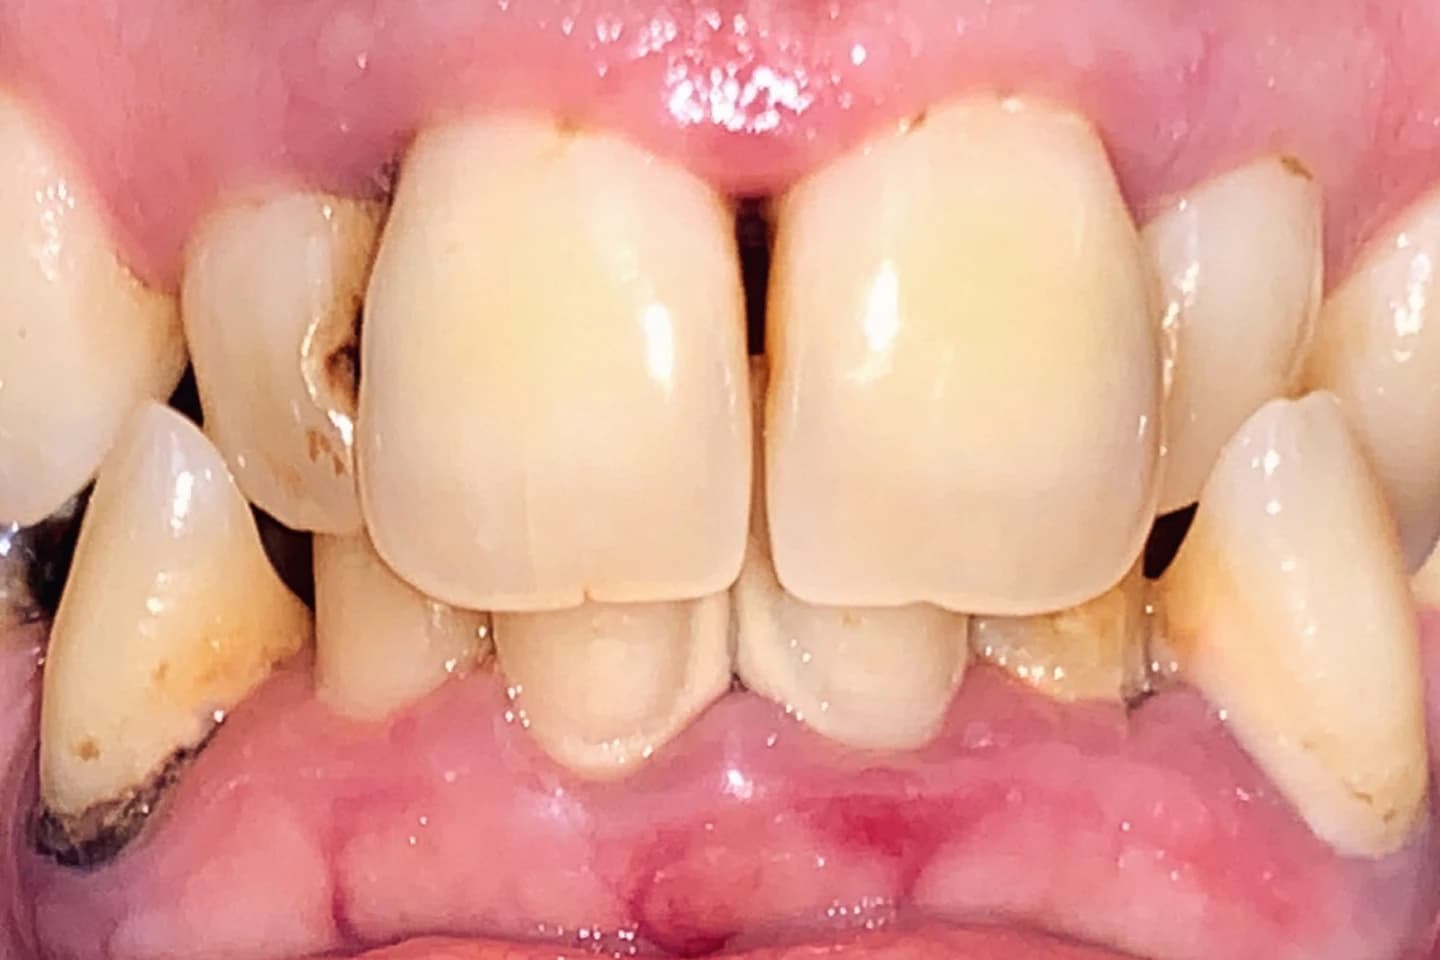

Fasete za zube - pre i posle

- Korigujte manje nepravilnosti i postignite blistav osmeh uz pomoć faseta. Pogledajte kako fasete mogu da transformišu vaš osmeh u samo nekoliko poseta.